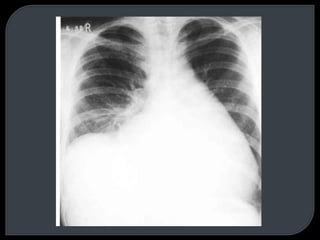

This document discusses x-rays and radiographic views. It begins with the discovery of x-rays by Wilhelm Conrad Roentgen. It then covers basic concepts like radiopacity and radiolucency. Several standard radiographic views are described like AP, PA, lateral, and decubitus. The document outlines how to analyze a chest x-ray using the ABCD method and lists common abnormal radiological signs. Radiographic technique factors like centering and inspiration level are also addressed.